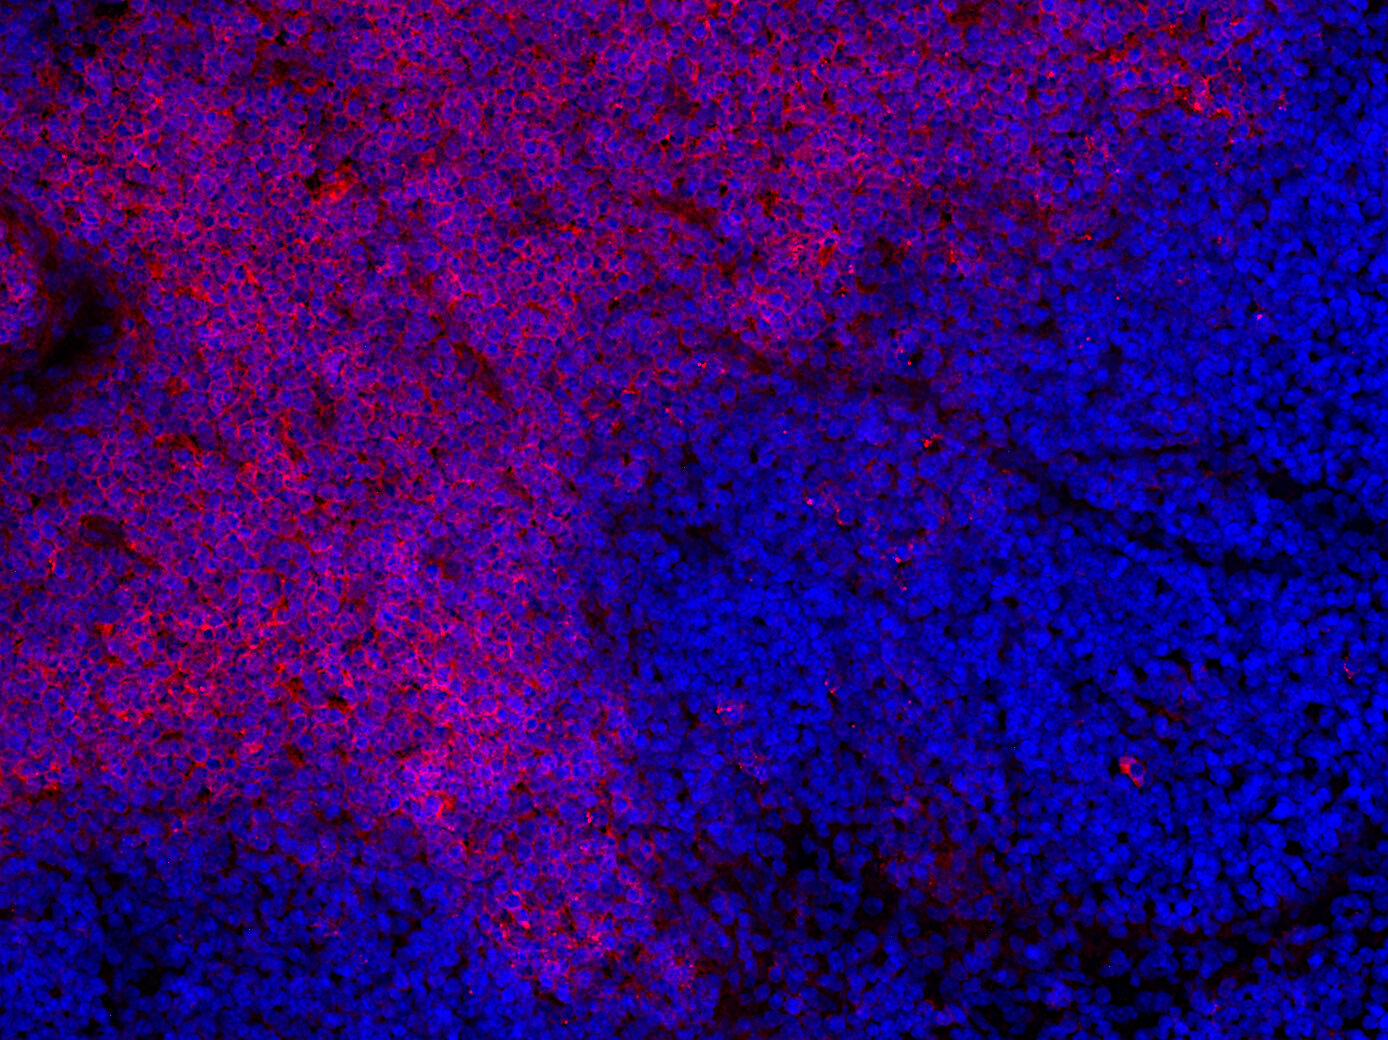

CD8 positive T-cells in FFPE mouse thymus section

IHC-P: 1 : 100 gallery

IHC-Fr: 1 : 200 (see remarks) gallery